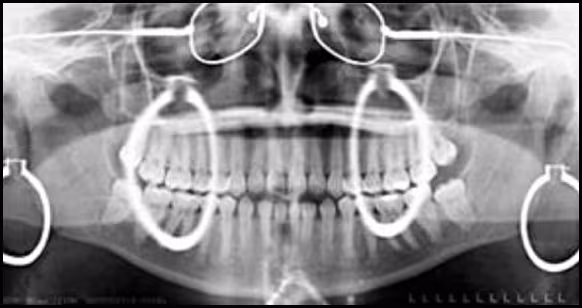

Figure 35. Panoramic Earring Ghost Images. This image illustrates the telltale signs of leaving several metallic objects on the patient, specifically earrings, glasses, and a neck chain. Note the ghost images produced by the earrings and their characteristic presentation.

Normal anatomic structures can also produce ghost images. Figure 36 demonstrates ghost images of the angle of the mandible which are projected to the other side and identified by the arrows.